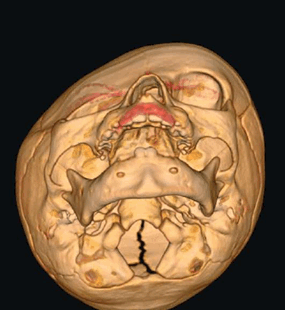

Скафоцефалия - стеноз сагиттального шва (от греч. scapho– «ладья»). Занимает первое место по числу встречаемости (0,2-1 случай из 1000 новорожденных). См. Рис. №3

При таком поражении имеет место сужение черепа по бокам за счет уменьшения роста теменных и височных костей и компенсаторный рост в переднезаднем отделах.

а) – форма черепа ребенка при скафоцефалии

б) - эндоскопическая коррекция (СКТ снимки)

в) – открытая реконструкция костей свода чрепа (СКТ снимки)